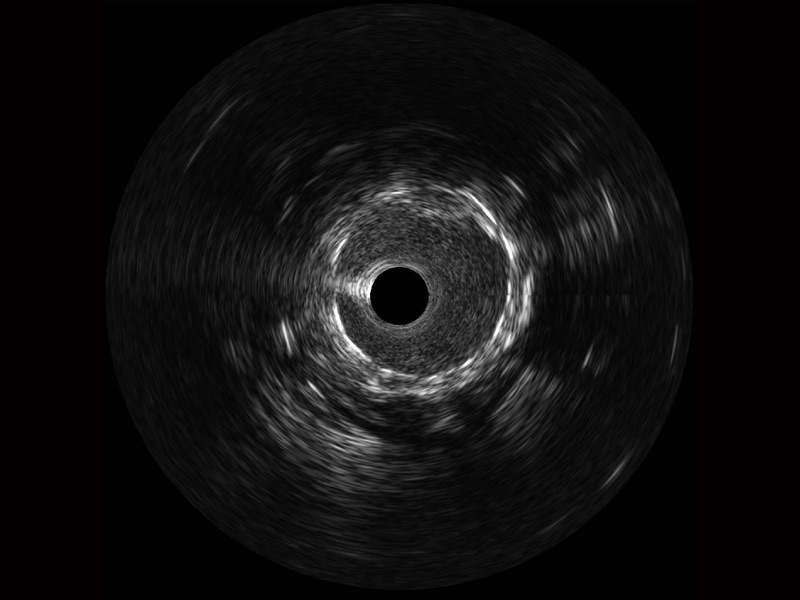

亚星官网宽频IVUS图像

传统IVUS图像

对比传统IVUS导管成像,亚星官网宽频IVUS图像的近场支架梁显影更细腻,远场中膜外血管仍清晰可辨,兼顾远中近,兼顾分辨力与穿透深度